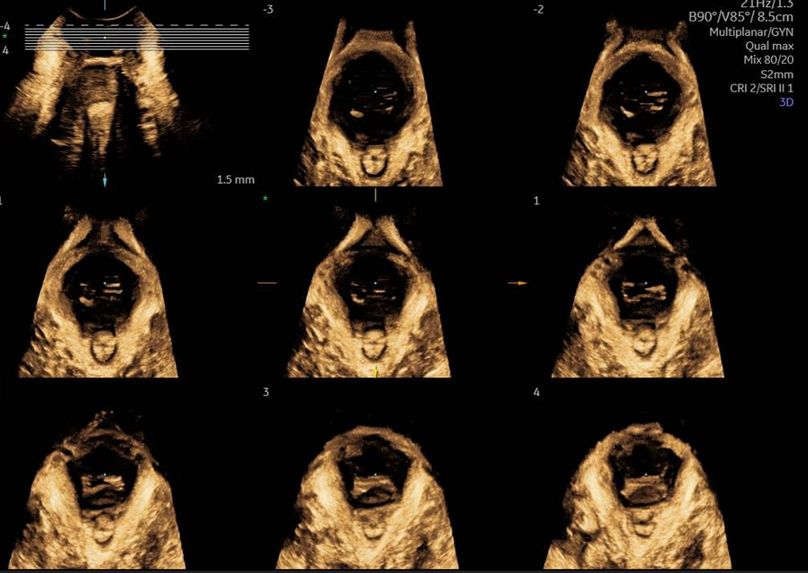

Eseguo in particolare ecografie ostetriche e ginecologiche anche in 3D e 4D per meglio identificare la problematica, offrire diagnosi precise ed un trattamento mirato e personalizzato.